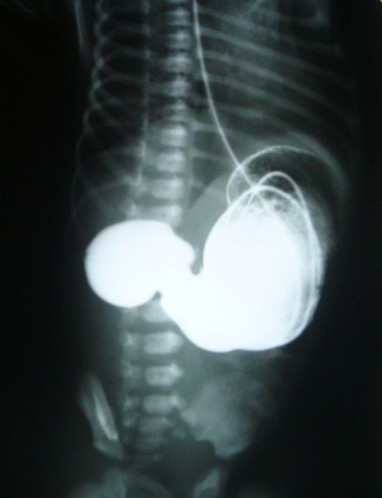

2014 | Keywords neonatal vomiting, plain film, ,

IMAGING OF NEONATAL VOMITING IN CORRELATION WITH CLINICAL AND SURGICAL FINDINGS

To correlate different surgical causes of neonatal vomitting with early radiological finding Read more